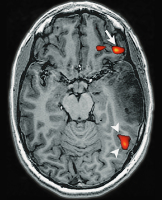

Brain tumour

Figure 3: Large high-grade tumour in the left temporal lobe of a right-handed patient. fMRI activation of a verb generation task is present in the expressive-language area in the inferior frontal gyrus (arrows), as well as in the receptive-language areas in the posterior temporo-parietal cortex (arrowheads) in the right hemisphere. No activation is seen in the left hemisphere. Upon surgery, a left-lateralised hemispheric language representation was found with ECM, as would be expected in a right-handed patient. The atypical lateralisation towards the right hemisphere found with fMRI is most likely due to a tumour (mass) effect decreasing the BOLD signal in the affected left hemisphere.

Keywords: brainfMRITumor